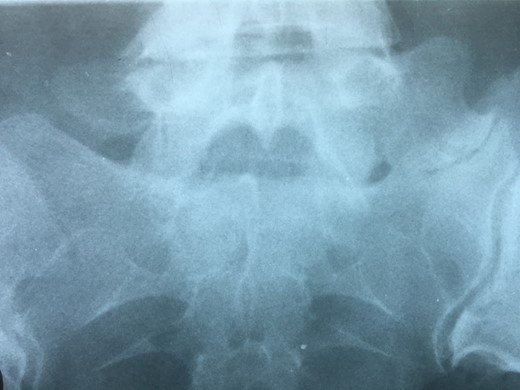

RMN of the patient showing smaller facets in the anomalous articulation and healthy disc compared to the supradjacent one (next figure).